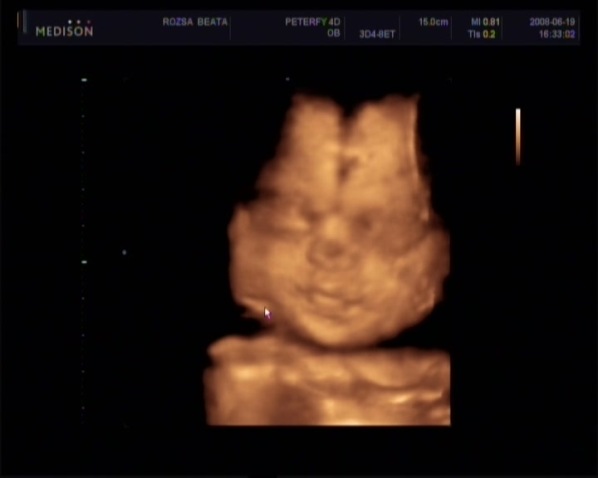

Voltam a melóhelyemen, tök jól esett a fogadtatás! Riadóláncban ment az értesítés, hogy ott vagyok, úgyhogy hamar ott volt a fél főosztály! Mindenki csak dícsért - végre-, megmutattam Bianka 4D-s képeit, őt is dícsérték.

Ja, a kiscsajsziról teszek fel 1 képet. Múlt héten készült: